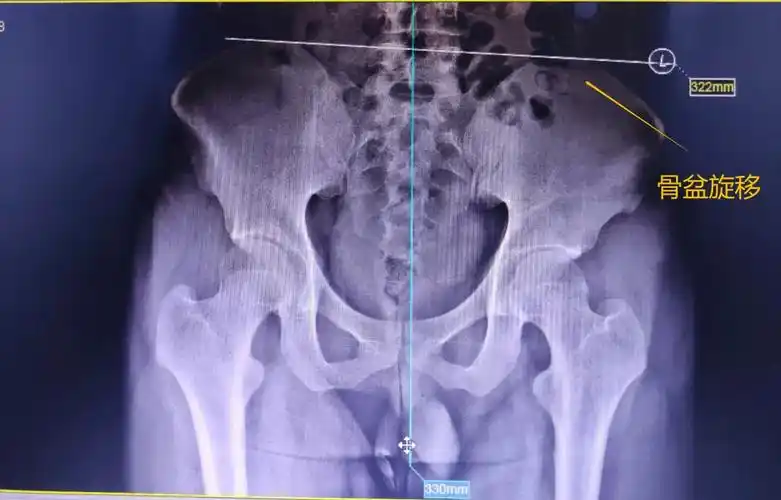

有一种腰腿疼痛叫骨盆旋移症